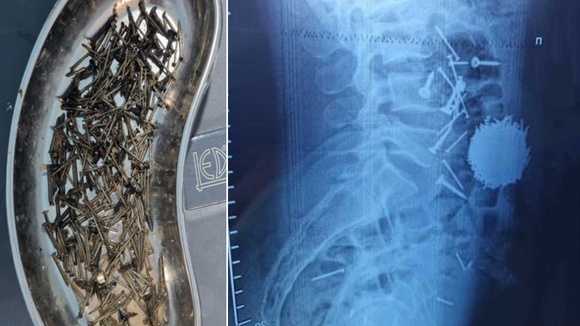

По результатам диагностики и лабораторных исследований у пациента в желудочно-кишечном тракте было выявлено большое количество металлических предметов — гвоздей и саморезов.

«Было принято решение о необходимости проведения экстренного хирургического вмешательства. После выполнения всех подготовительных процедур была проведена операция методом лапаротомии и гастростомии. Из брюшной полости пациента удалось извлечь значительное количество металлических предметов — около 200 граммов. Операция длилась около часа», — сообщил врач высшей категории медцентра Юлдош Кулиев.